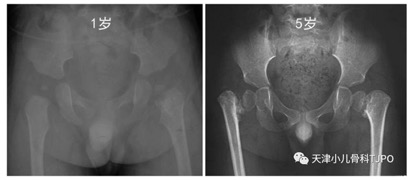

5岁男孩,走路跛行摇摆半年

这其实是一例发育性或者也称为先天性髋内翻。在1岁的X线片中已经可看到左侧股骨颈内侧的异常。股骨颈与头骺间增宽的透亮带其实就是增宽的骺板线,容易被误认为骨折线,股骨颈内下方的骨化不规则三角形区域是部分病例的特征性表现。